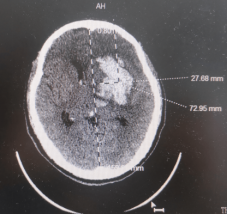

71岁男性,突发右侧偏瘫失语26小时,生命征平稳,昏睡,可遵嘱活动左侧肢体,GCS评分13分,右侧肢体肌力0级,病理征阳性。

CT显示左侧基底节区不规则脑出血,有多处“岛征”

考虑血肿“岛征”明显,极易再出血,为安全起见在上下两靶点中间选择靶点,单管引流。可能对血肿的扰动少,减少再出血概率。